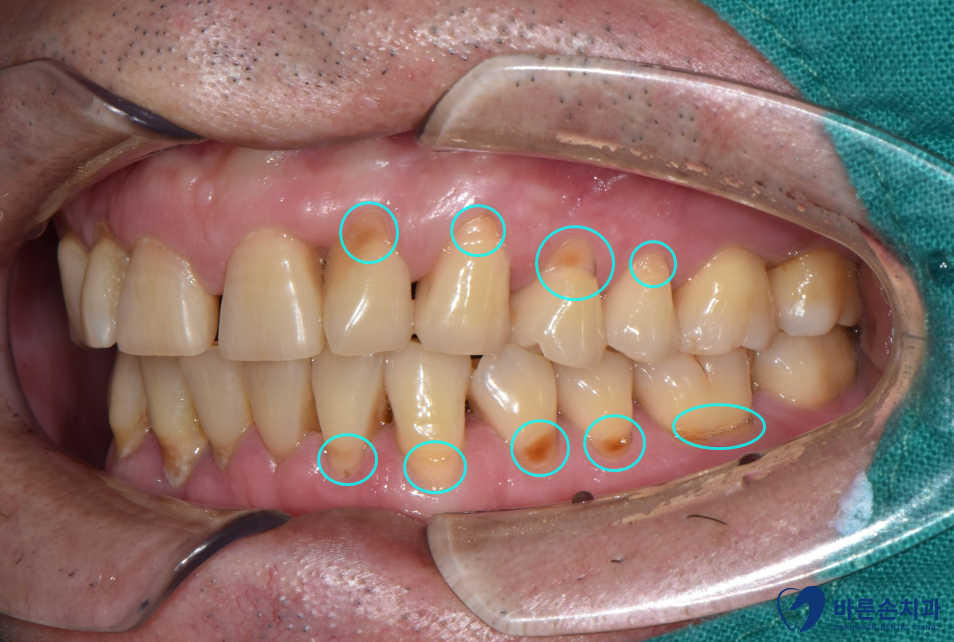

Befoer 23.09.07

<치경부 마모증>

치아와 잇몸 사이 경계부가 마모되어 파이는 증상입니다.

어금니 쪽을 보면 치아가 뚝뚝 떨어져 나가서 파여있는 모습이 보이시죠?

이 상태로 방치하게 되면 더 파이게 되고

치아가 시린 증상도 생기기 때문에

그렇게 되기 전에 미리미리 때워서 사용하시는 게 좋아요~